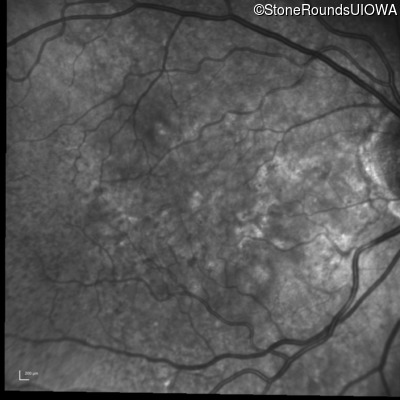

Pseudoxanthoma Elasticum (IID2)

Age at visit: 58 years

Diagnosis & molecular findings

Disease Gene Allele 1 variant(s) Allele 2 variant(s) Inheritance mode

Pseudoxanthoma Elasticum ABCC6 Gly928 del4tacGGCA IVS21+1 G>T AR